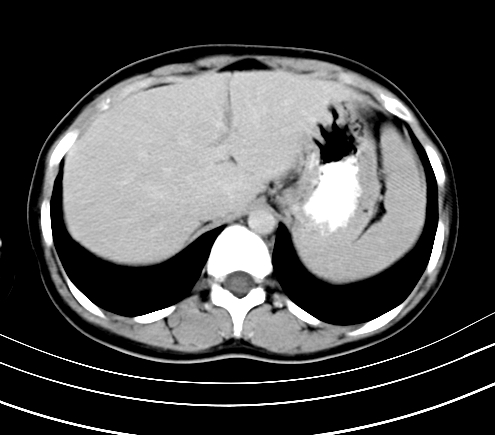

延时5分钟